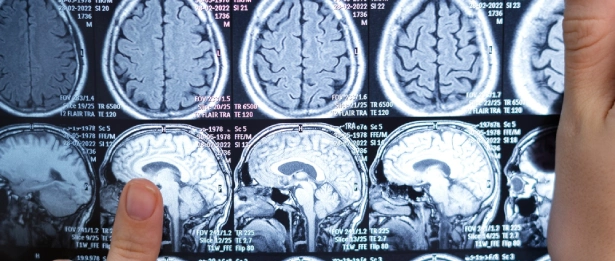

Nöroradyoloji, özellikle beyin, omurilik ve sinir sistemine ait yapıların detaylı değerlendirmesinde kritik bir rol oynar. Nöroradyologlar, manyetik rezonans görüntüleme (MR), bilgisayarlı tomografi (BT), anjiyografi ve nükleer tıp tekniklerini kullanarak çeşitli nörolojik hastalıkların tanısını koyar ve bu hastalıkların tedavi planlarının oluşturulmasına katkı sağlar.

Nöroradyolojik değerlendirme, inme (felç), beyin tümörleri, epilepsi, multiple skleroz (MS), damar malformasyonları, travmatik beyin hasarları ve omurga hastalıkları gibi pek çok önemli nörolojik durumun doğru ve zamanında teşhisinde hayati öneme sahiptir. Özellikle akut inmelerde beyin damarlarının anjiyografik görüntülenmesi ve pıhtının yerinin belirlenmesi tedavinin hız ve başarısı açısından belirleyicidir. Bu nedenle nöroradyoloji, acil ve yoğun bakım ortamlarında da önemli bir rol oynar.